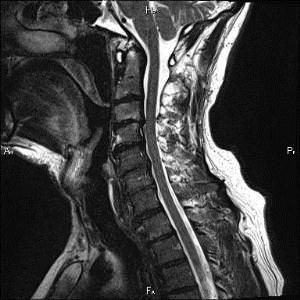

В современное время диагностировать заболевание не составляет особого труда, ведь симптоматика заболевания ярко выражена. Врач невролог при осмотре может установить диагноз, который потом при помощи МРТ или КТ будет подтвержден, или же опровергнут. С помощью МРТ можно определить размер грыжи, ее точное расположение, исключить любую другую патологию.